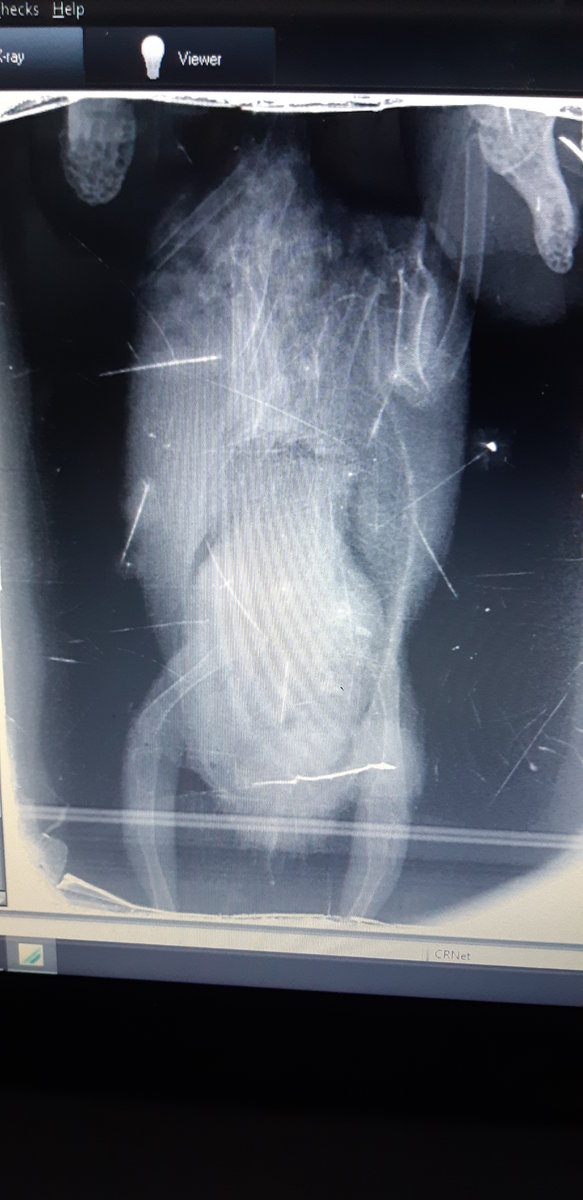

12 октября обращалась в ветклинику: На осмотре не пикнул, вес 29,8 гр. В мазке из зоба и из кала ничего патологического не обнаружили. Сделали рентген, упитанность хорошая, сказали, что совсем чуть чуть увеличены границы печени, но не критично, легкие и кости в норме. Рекомендовали в качестве витаминов давать Спирулину и увлажнять воздух (Также выписали рекомендации, если начнет чихать, появятся истечения из носа, будет вялый).

Прилагаю фото рентгена от 12.10, фото птицы и помета от 10.12

20211012_135601.jpg